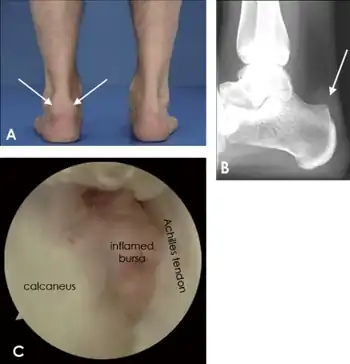

a,b)Individual with retrocalcaneal bursitis c) endoscopic view of retrocalcaneal bursitis.